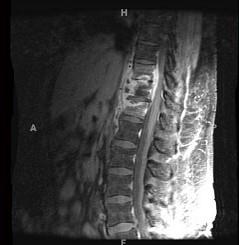

问题 女,67岁,突发右侧背痛半月余,请结合影像学检查,选择最可能的诊断 ( )

选项 A、脊椎结核 B、强直性脊柱炎 C、椎体压缩骨折 D、脊柱转移瘤 E、化脓性脊柱炎

答案 A